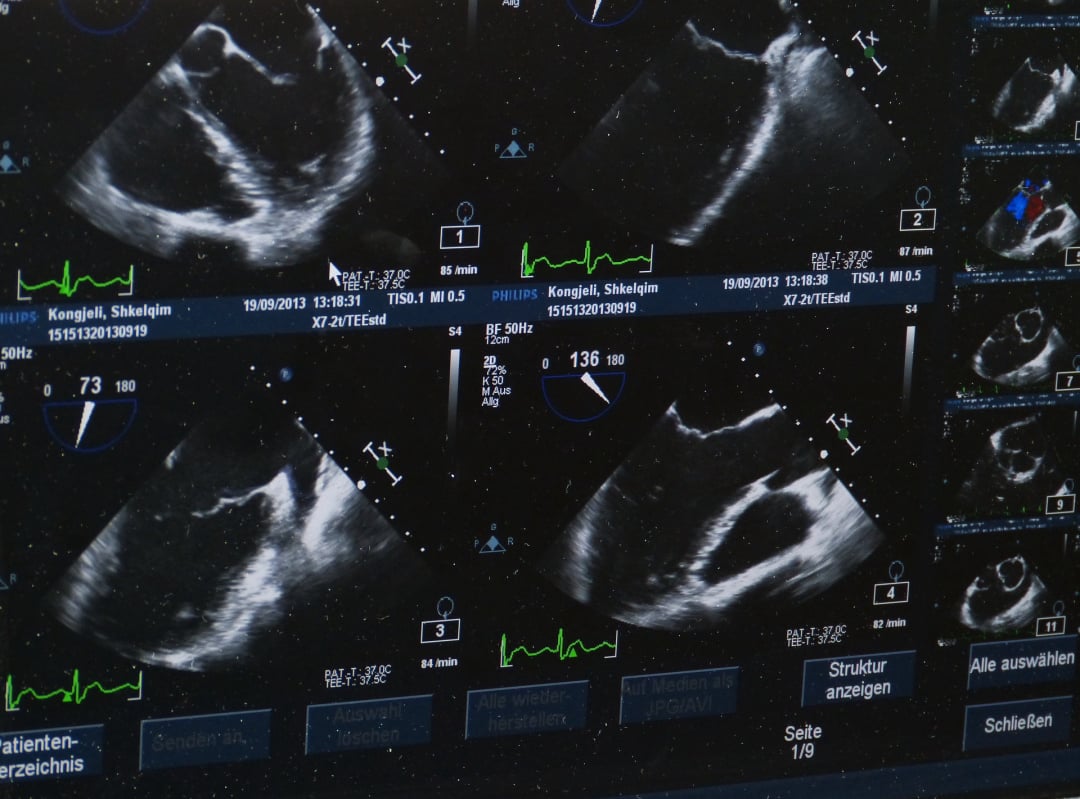

- Echokardiográfia szívizomzat és szelepek részletes vizsgálatára.

Vizsgálataink magukban foglalják az EKG-től kezdve az echokardiográfiát, biztosítva, hogy minden apró részletre fény derüljön. Szakembereink nemcsak az esetleges problémákat azonosítják, hanem egyéni életmódbeli tanácsokkal is ellátják Önt a szív egészségének megőrzése érdekében.

**Érezze Meg a Szíve Dobogását - Kardiológiai Szívultrahang Vizsgálatunkkal!**

Tudja meg, hogyan működik a szíve a részletekig szakértő kardiológiai szívultrahang vizsgálatunkkal! A modern orvostechnológia segítségével szívünk titokzatos világába nyerhet betekintést, és minden rezgését szinte érezheti.

Szívultrahang vizsgálatunk nem csupán egy egyszerű diagnosztikai eljárás - ez egy élmény, ahol a precíziós technológia és a tapasztalt szakemberek összefonódik a szív egészségének megőrzése érdekében. Lépjen be a szív frekvenciáinak világába, miközben mi minden apró részletre odafigyelünk!

Rugalmas időpontokkal és gyors eredményekkel várjuk Önt a szívultrahang vizsgálatunkon. Éljen a lehetőséggel, és kezdjen utazást szívének egészsége felé velünk! Hozza el szívét hozzánk, és hagyja, hogy a modern orvostudomány és a szívünk iránti szenvedélyünk gondoskodjon Önről. Egészséges szív, boldogabb élet - kezdje most!